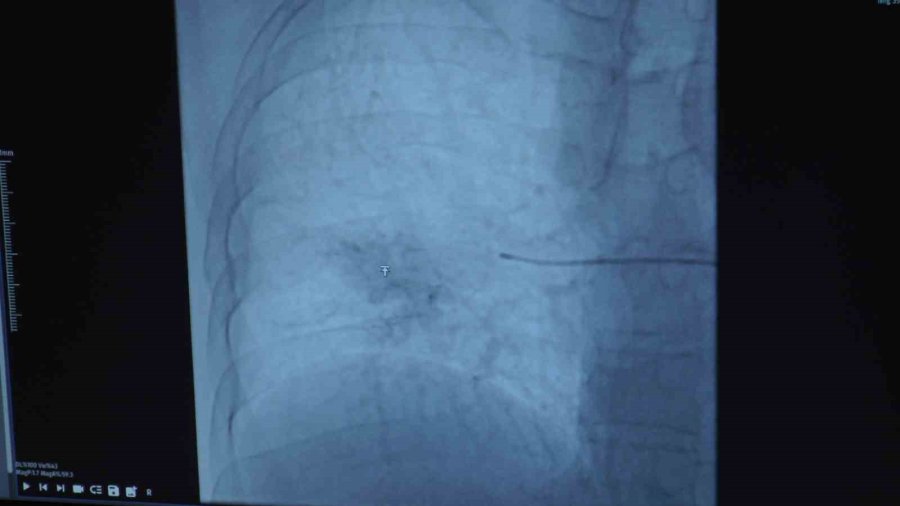

Girişimsel Radyoloji Bölümü'nden Dr. Oğuz Aslan da Behçet hastalığı olanların kanama durumunda akciğer atardamarlarında bir anevrizma olabileceğini akıllarında bulundurması gerektiğini söyleyerek, "Osman bey bize göğüs hastalıkları tarafından yönlendirildi. Kendisinin Behçet hastalığı tanılı, tekrarlayan akciğer kaynaklı kanamaları mevcuttu ve pulmoner anevrizma dediğimiz bir baloncuk mevcuttu Behçet hastalığında sekonder olarak nadir gelişen bir durum olarak. Hastamıza bu anevrizmanın kapatılabileceğini ve işlemin nasıl olduğunu, risklerini anlattık. Kendisi de düşündü ve tedavi olmaya karar verdi. Öylelikle bir teşhise dair anjiyoya aldık kendisini. Tedavi planımızı belirledik ve ikinci bir seansta kendisine bu büyük damarları tıkamakta kullandığımız vasküler tıkaçlar dediğimiz materyaller ile anevrizmasını kapattık. Anevrizma kapatmanın aslında birçok yöntemi var ama hastamızın besleyici damarı çok büyük olduğu için bunları daha büyük damarları tıkamak için kullandığımız materyalleri kullandık. Bir gün serviste yattı ve ertesi gün taburculuğunu sağlamış olduk. Bizim gördüğümüz hastaların çoğu Behçet hastası ve bu hastaların yüzde 1-2'sinde görülebiliyor bu komplikasyon. Embolizasyon işlemi sonrasında hastamızın bu mevcut durumu tamamen kapandığı için en azından bu anevrizma özelinde ekstra bir akciğer kanaması hemoptizi ihtimali ortadan kalkmış oldu. Şöyle söyleyebiliriz; Behçet hastalığı tanısı olan hastaların öksürükle ağzından kan gelmesi durumunda akciğer atardamarında bir anevrizma olabileceği akılda bulundurulmalı ve bunun tedavisi için gerekli başvurular da yapılmalıdır. Burada hastalar Girişimsel Radyoloji Kliniği'ne de başvurabilirler ya da göğüs hastalıkları tarafından da bize yönlendirilebilirler" ifadelerini kullandı.